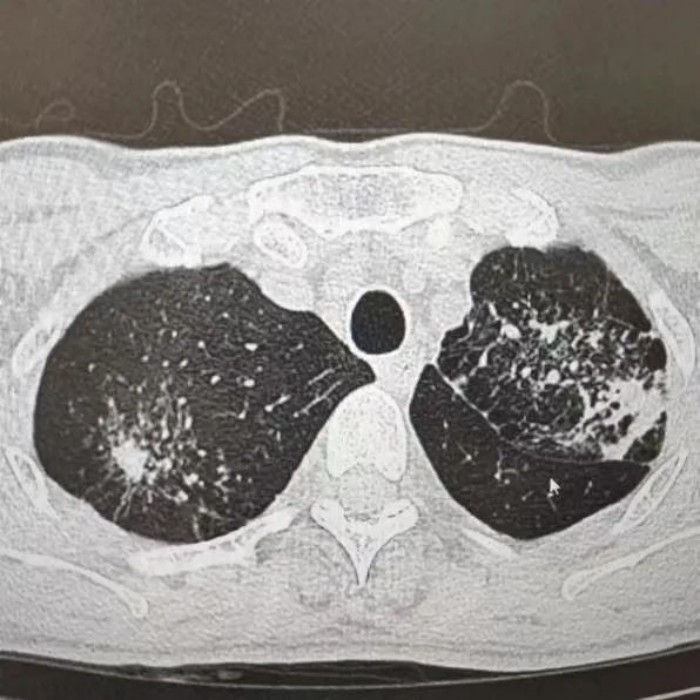

很快,CT報(bào)告提示“升結(jié)腸、回盲部及回腸末端腸壁增厚伴局部淋巴結(jié)腫大,考慮腸結(jié)核”。之后,進(jìn)一步做了胸部CT檢查,提示“肺部浸潤(rùn)灶:肺結(jié)核考慮”。

經(jīng)過痰化驗(yàn)及腸鏡檢查病理活檢,葉師傅被確診為“肺結(jié)核、腸結(jié)核伴腸梗阻”。